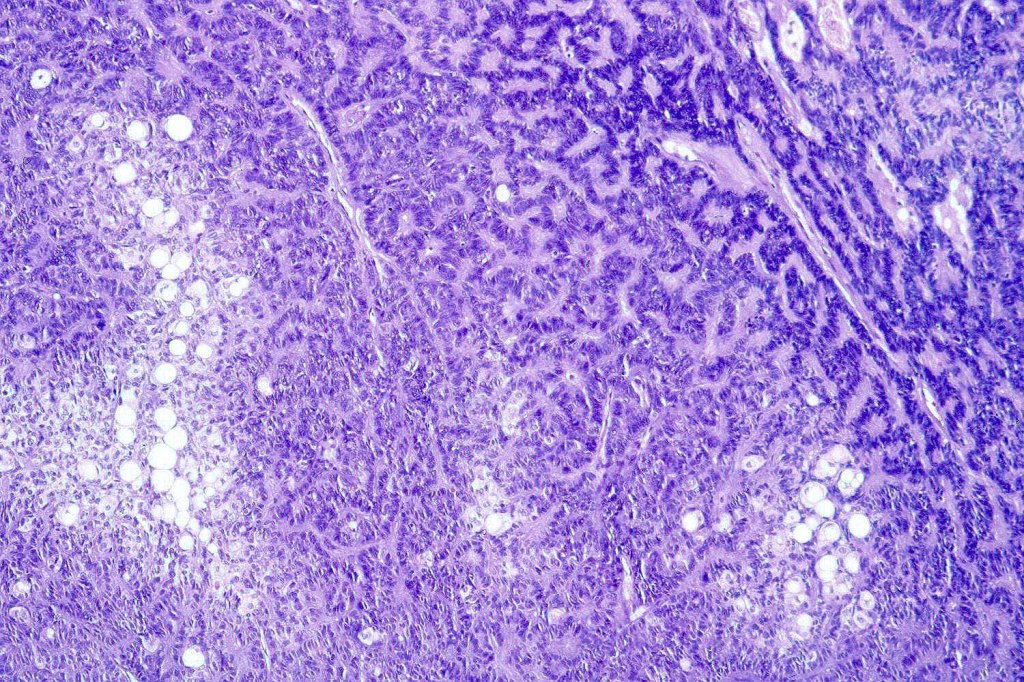

Histological features

•Variable continuity with epidermis

•Multinodular with surrounding collagenous stroma

•Random distribution of basaloid cells & sebocytes (<50% sebocytes)

•Duct formation, often with holocrine secretion generally present

•Mitoses sparse to conspicuous

•Absent peripheral palisading & retraction artifact

•Cystic variant

•Subtypes include rippled pattern, carcinoid-like & reticulated